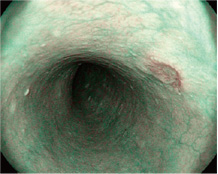

食道

胃

大肠